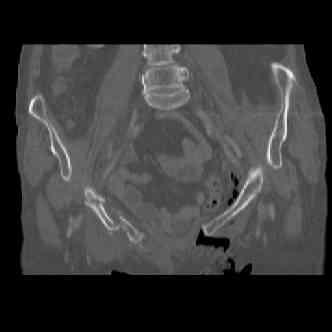

attached are images of a 70 year old female after peds versus car. her own car ran her over.

injuries are limited to the pelvis. left rami open and visible in a 10cm vertical laceration just lateral to left labia majora. wound is grossly clean. no vaginal and no urinary issues. CT scan shows widening of both SI joints anteriorly but I think this is vertically stable pattern.

pt treated that night with I/D and supra-acetabular frame to close the ring. consideration was given for SI screws bilateraly, but given time of night and other factors decision made not to proceed.

so the question is what next operatively if anything? concerns are infection, nonunion anteriorly and possible incompetence of the pelvic floor which may lead to prolapse issues. right rami are comminuted and plating may entail ilioinguinal approach to extend plate laterally to right iliac wing. retrograde screw up right rami is an option but I am not convinced it will add much. adding SI screws very doable, but major concern is restoring anterior ring. so far wound is clean and closed over a drain, and I have no plans to open it back up and wash again.

maintaining pelvic alignment in ex-fix in 70 yo female for any length of time may be challenging.

any thoughts? would anyone plate the pubic symphysis to close the gap and leave the more lateral rami fractures alone? the most recent pelvic case on this website involved pts with suprapubic catheters and antibiotic options including resorbable beads. I wonder how many people would plate and place antibiotic beads. thanks.

attached are several CT cuts. please let me know if you need more. the CT is pre-pelvic ex-fix placement.

Thank you.